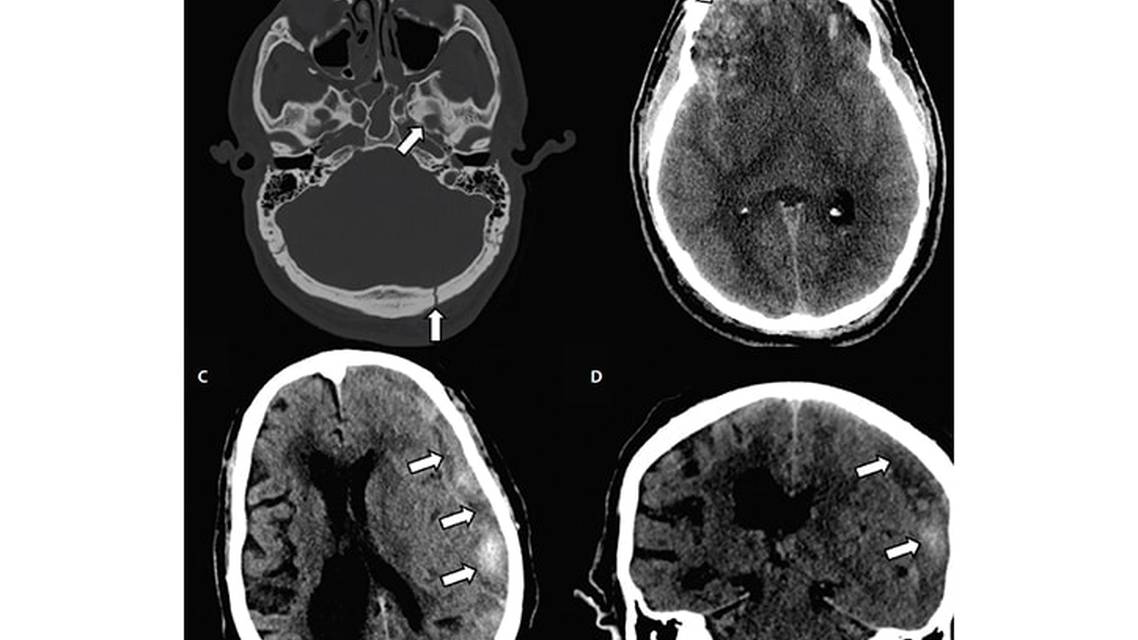

A subdural hematoma (SDH) is a collection of blood between the brain and the dura, typically caused by traumatic injury to the bridging veins in the subdural space.18 Often found along supratentorial convexities, SDH may also occur along the tentorium itself, the falx cerebri, and, less commonly, in the posterior fossa. On CT, a SDH classically appears as a concave-shaped hematoma crossing suture lines (Figures 1C, 1D, and 3C). Unlike EDHs, acute, subacute, and chronic SDHs are all likely to be discovered at initial imaging, depending on the clinical scenario. An SDH can appear as hyperdense, isodense, hypodense, or mixed density depending on the age of the blood within the hematoma itself. Depending on size, SDHs may cause significant mass effect with midline shift and even herniation. Large SDHs are easily identified on CT, but smaller hematomas are better identified on MRI where they will appear as extra-axial collections with T1 and T2 signal characteristics varying with the age of the bleed (Figure 3C).19 These smaller SDHs not readily apparent on CT are unlikely to be clinically significant, but MRI can accurately confirm the diagnosis and age blood products within the hematoma.

Traumatic subarachnoid hemorrhage (SAH) refers to blood products within the subarachnoid space occurring from traumatic injury to small subarachnoid vessels. Traumatic SAH is a common finding in the setting of TBI.20 Unlike aneurysmal SAHs that are typically seen in the basal cisterns and Sylvian fissures, traumatic SAHs are smaller and tend to occur primarily along cortical sulci. Acute traumatic SAHs are seen on CT as curvilinear hyperdensities. If a SAH is small, subacute, or chronic in nature, it may be difficult to identify on CT. In such cases, MRI has been shown to have superior sensitivity for identifying these hemorrhage.21,22 An SAH will appear as FLAIR and SWI signal abnormality (Figure 3C).22

Cerebral contusions are caused by forcible impact of the brain against the skull. The contusion occurs in the parenchyma and may be on the same (coup injury) or opposite (contrecoup injury) side of the trauma. Cerebral contusions are typically hemorrhagic with associated edema and appear as hyperdense foci with scattered or surrounding hypodensities on CT (Figures 1B and 3A,B).23,24 Nonhemorrhagic contusions may also occur and are better seen on MRI.24 Parenchymal contusions tend to occur in the temporal and frontal lobes and often demonstrate expansion on interval imaging.25

Diffuse axonal injury (DAI) is a primary injury to axons at the at gray- and white-matter junctions, corpus callosum, deep white matter, periventricular regions, hippocampi, and brainstem.26 Shearing forces during acceleration-deceleration injury cause DAI, which may appear as small hyperdensities on CT, although MRI is more sensitive for detecting DAI.24 Lesions of DAI typically appear as foci on SWI/GRE, FLAIR, and ADC signal abnormality within the white matter (Figure 3D). Prognostic value of MRI is high in this setting because DAI lesion burden is correlated with worse prognosis.27